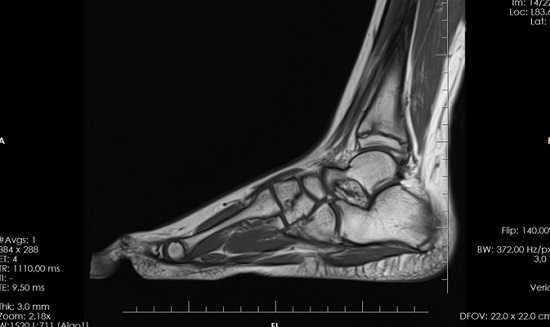

МРТ стопы. Остеомиелит таранной и большеберцовой кости с наличием обширной зоны деструкции костной ткани.

КТ стопы. Посттравматический хронический остеомиелит пяточной кости с наличием секвестра (красная стрелка) и свищевого хода (синяя стрелка).